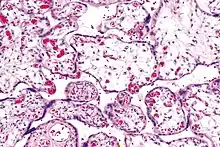

| Micrograph of villous immaturity. H&E stain. | |

Immature chorionic villi are larger and have more central blood vessels; thus, the diffusion distance for gas and nutrient exchange is larger and, therefore, placental function is impaired.

High mag.